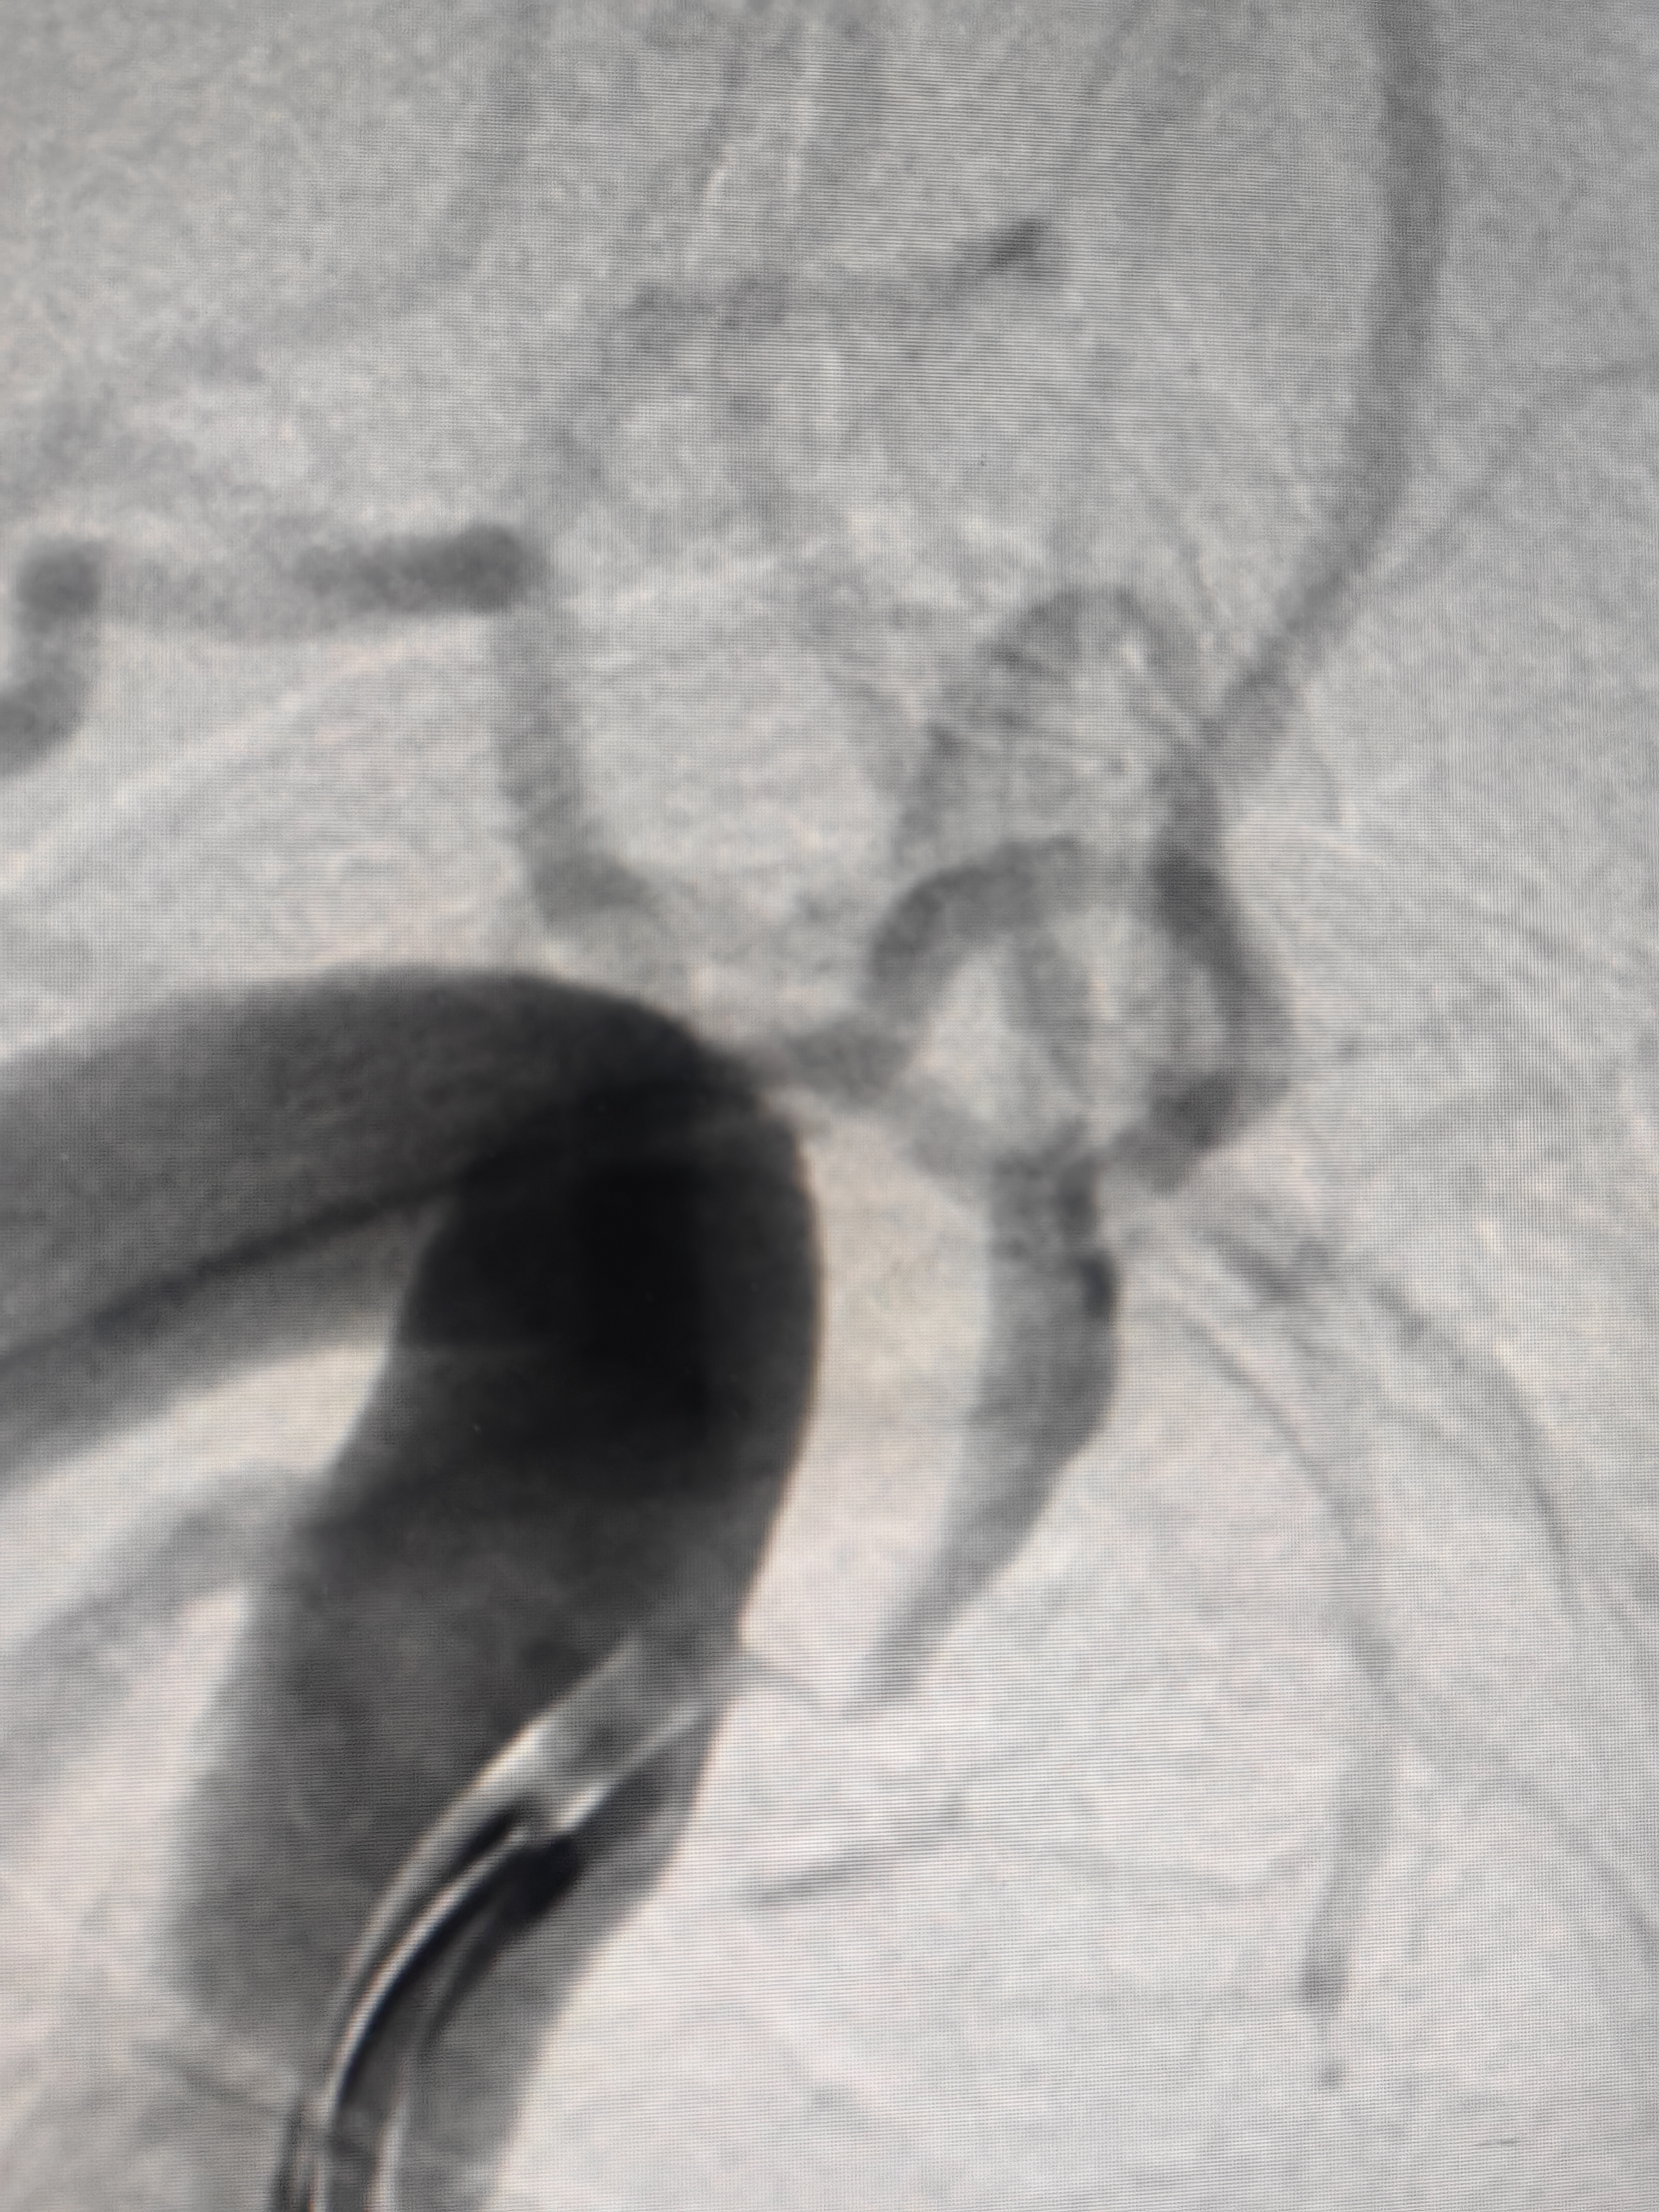

我以为微导管通过会稍困难,结果还算顺

接下来的简单了,微导管造影,3m导丝交换,小球囊预扩,支架到位,定位,释放,造影: